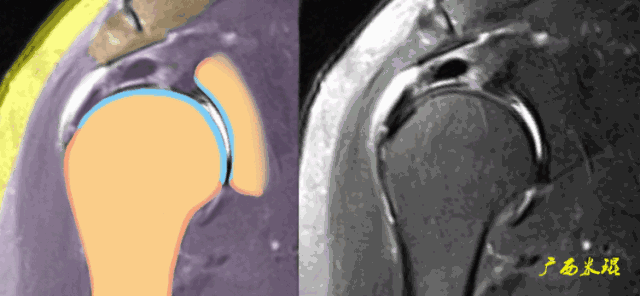

各个序列肩袖均表现为均匀的低信号,是肌腱的延续。

Grade0:肩袖形态正常,连续性完好,肩袖信号正常。

Grade1:肩袖形态正常,连续性完好,肩袖内信号异常。

Grade2:肩袖连续性存在,形态异常(肩袖变薄/变厚,形态不规则)。

Grade3:肩袖外形异常,连续性中断。

在Zlaikin分级中,0级是正常肩袖,1、2级代表退变,3级为撕裂,也就是真正的肩袖损伤。